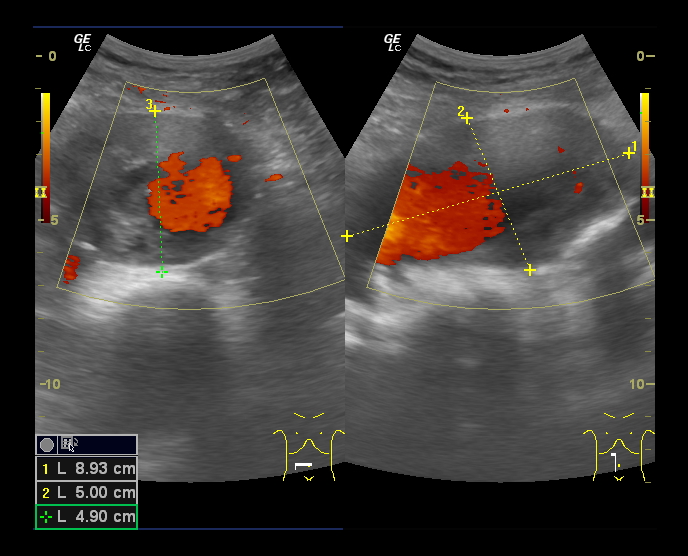

En Ecografía Clínica se aprecian, en la porción distal de la Aorta, imágenes sugestivas de aneurisma de Aorta abdominal con medidas aproximadas de 5.3 cm (anteroposterior) x 9 cm (longitudinal) con importante trombo intramural.

Diagnóstico diferencial: A la exploración física puede confundirse con otras masas abdominales como esplenomegalias o tumores. Con la eografía, la localización y captación doppler así como la pulsación característica hacen que resulte complicado confundir el diagnóstico.